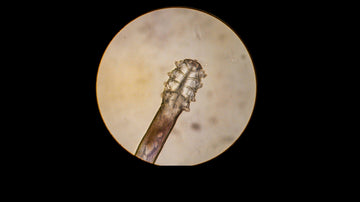

Demodex is one of the billions of tiny organisms that are too small to see with the naked eye, which is probably a go...

“Eyelash mites” is the common name for Demodex mite species that inhabit the hair follicles or oil glands around your...

Demodex in humans are different from the ones in animals. The Demodex mite is a tiny arachnid (8 legged) parasite tha...

Eyelash mites are almost certainly living off of skin cells and sebum of your face. These tiny eight-legged arachnids...